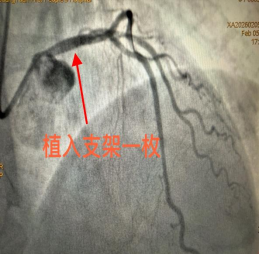

时间就是生命,时间就是希望。面对这一危急病例,科室立即启动急诊绿色通道,以最快速度全力推进诊治。急诊冠脉造影检查结果令人心惊:患者冠状动脉左主干狭窄程度高达95%。左主干是心脏冠状动脉的核心血管,被称为“生命主干道”,起源于主动脉根部,分支为前降支和回旋支,负责为左心室(心脏主要泵血结构)提供 75% 的血液供应。左主干病变是指冠状动脉左主干(LM)发生≥50%的狭窄,属于高危冠心病范畴。该病症病情凶险,若处理不当,极易引发猝死、大面积心肌梗死、心源性休克等严重后果。

该患者左主干狭窄95%,病情凶险程度极高,堪称“生死一线间”,需立即手术。在征求患者及家属意见后,各部门高效协同联动,着手准备手术。

手术台上,每一个操作都精准无误,每一步决策都果断坚定。在生死竞速的关键时刻,心血管内科三病区杨金勇副主任团队默契配合、沉着应战,凭借精湛的技术成功为患者实施介入治疗,开通了重度狭窄的血管,恢复了心脏正常供血。整个手术过程十分顺利,患者胸痛症状迅速缓解,生命体征趋于平稳,成功脱离生命危险,目前已顺利出院。